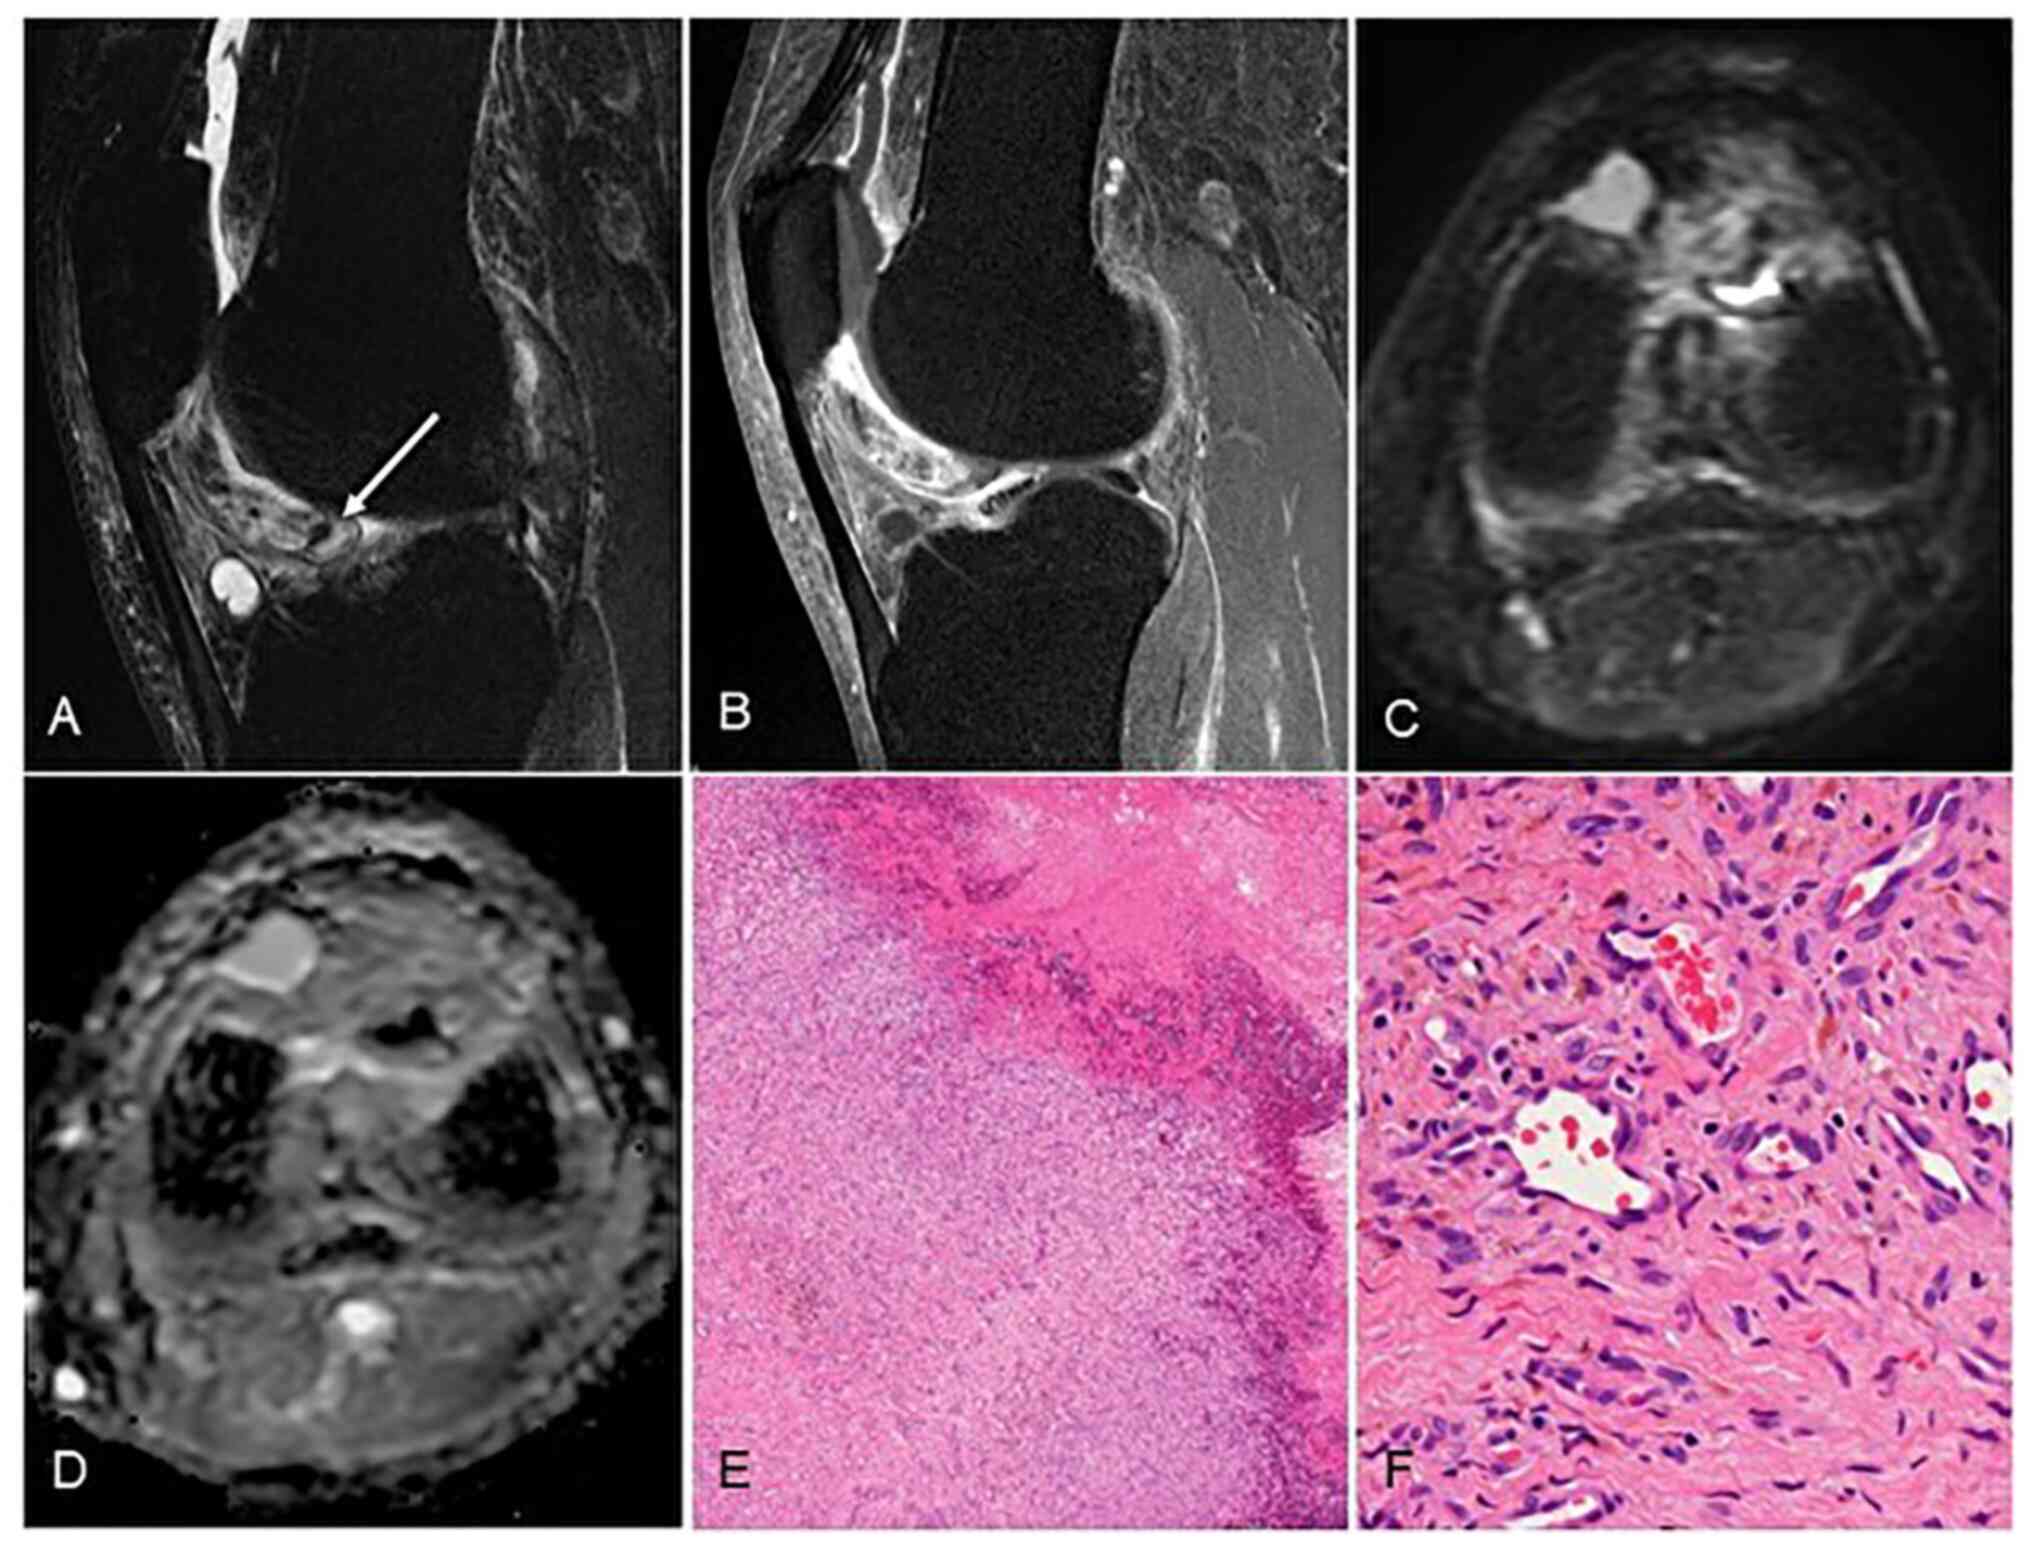

Figure 1

Venous synovial hemangioma (patient #4). On magnetic resonance imaging, (A) T1-WI (sagittal view) showed low-signal intensity without a signal void and (B) T2-WI (sagittal view) showed high signal intensity containing small signal void (arrow). (C) Gadolinium-enhanced T1-weighted fat-suppression imaging (sagittal view) showed heterogeneous staining of the tumor. Pathologically, the vascular smooth muscle is thickened and vascular lumen is dilated: (D) low-power field (magnification, x20), H-E staining; (E) high-power field (magnification, x200), H-E staining. Slow blood flow is prone to forming thrombus and phleboliths. H-E, hematoxylin and eosin.

Capillary hemangioma (patient #9). (A) On magnetic resonance imaging, T2-weighed fat-suppression imaging showed high signal intensity containing small signal void (arrow). (B) Gadolinium enhancement showed heterogeneous staining of the tumor. (C) DWI showed low-signal intensity in the tumor and (D) high apparent diffusion coefficient (ADC) value of 2,184/mm2/sec. Microscopic findings show small vascular lumen, which was less likely to form thrombus or phleboliths, and this tumor was difficult to diagnose without microscopic confirmation: (E) low-power field (magnification, x20), H-E staining; (F) high-power field, (magnification, x200), H-E staining. H-E, hematoxylin and eosin.

Based on the pathological findings of surgical specimens, the diagnoses were venous hemangioma (Fig. 1), capillary hemangioma (Fig. 2), cavernous hemangioma (Fig. 3), in three patients each. Venous hemangiomas have thickened vascular smooth muscle and a dilated vascular lumen. Because of slow blood flow, they are prone to forming thrombi and phleboliths. Capillary hemangiomas have a small vascular lumen and are less likely to form thrombus or phleboliths. Microscopy should be used for diagnosis. In cavernous hemangiomas unlike the venous hemangiomas, vascular smooth muscle is absent. The size of the intra-tumoral vascular lumen differs depending on the subtype of hemangioma.

The pathological diagnosis of synovial hemangioma is classified into the venous, arteriovenous, cavernous, and capillary subtypes (4). Venous synovial hemangiomas have thick vascular smooth muscle and a dilated vascular lumen. Cavernous synovial hemangiomas also have a dilated lumen, but unlike the venous subtype, they are differentiated by the absence of smooth muscle in the vessel wall. In both of these subtypes, the dilated lumen slows the blood flow and increases the formation of a thrombus and/or phleboliths compared to the capillary subtype, which has a smaller lumen. In the present patient series, the presence of phleboliths was confirmed by plain radiography and MRI in only two cases, both of which were the cavernous subtype (Fig. 2). On the other hand, capillary subtypes do not form a thrombus or phleboliths, because of their narrow lumen. It is thus difficult to diagnose capillary subtypes as hemangiomas without microscopic confirmation.

In the present series, diffusion-weighted imaging (DWI) was performed in one of the capillary subtype cases. The DWI showed low signal intensity in the tumor and the high apparent diffusion coefficient (ADC) value of 2,184/mm2/sec, excluding the area with high signal intensity that was thought to be post-hemorrhage changes (Fig. 3). Our review of eight cases of D-TSGCT of the knee that were treated at our institute between 2006 and 2021 revealed that the MRI findings revealed high signal intensity in DWI and the low mean ADC value of 770/mm2/sec. Usually, in the case of a solid or malignant tumor, cell proliferation causes an increase in intracellular structures and a narrowing of the stroma, which restricts the movement of water molecules, resulting in a low ADC value. D-TSGCT is a synovial tumor with a high proliferation of tumor cells and restricted movement of water molecules. Conversely, synovial hemangioma is an angioproliferative disease in the subsynovial layer, and thus the movement of water molecules in the lumen and stroma is not as restricted as in D-TSGCT, and its ADC may be higher than that in D-TSGCT. The present case series raises the possibility that DWI and ADC values may be important differentiators between synovial hemangioma and D-TSGCT. On the other hand, the importance of enhanced MRI in diagnosing synovial hemangioma was not observed in this series.